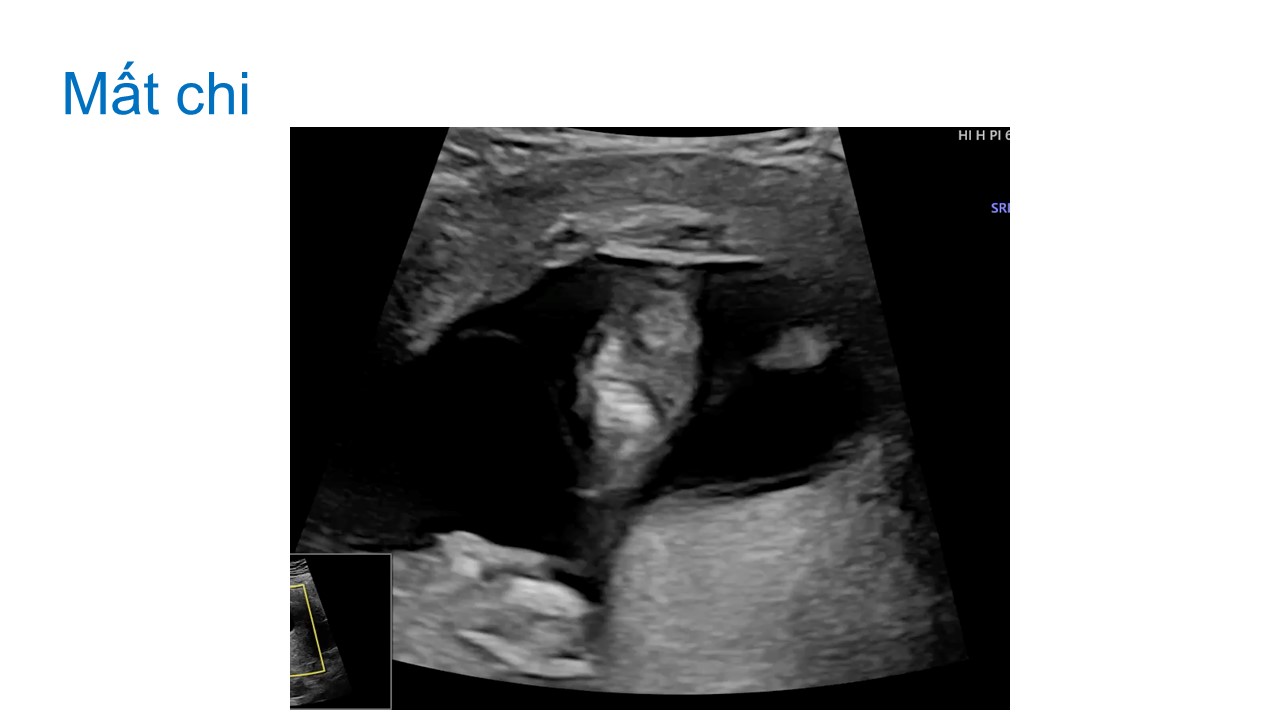

Siêu âm hình thai học quý I

Từ khóa: Siêu âm hình thai học quý I